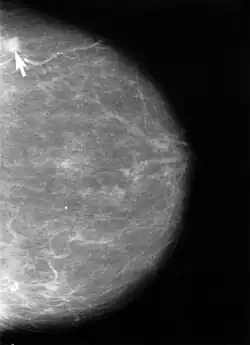

La mammographie est une modalité d'imagerie médicale mettant en œuvre la radiographie des seins, en vue de dépister des anomalies et le plus souvent, de dépister des cancers du sein.

Elle permet d'obtenir des images des tissus intérieur et ainsi de détecter au plus tôt d’éventuelles anomalies, notamment des nodules, qui peuvent être signes d'un cancer du sein.

Pour réaliser cet examen, le manipulateur en électroradiologie médicale utilise un mammographe. Cet appareil se compose d'un générateur de rayons X de faible énergie (entre 20 et 50 keV) et d'un système de compression du sein. La radiographie était auparavant réalisée sur des films argentiques ou sur des systèmes de radiologie digitale de haute qualité (pixels de 50 µm maximum et détecteurs de grande Detective Quantum Efficiency (DQE).

L'examen consiste à comprimer à tour de rôle les deux seins puis à les exposer à une faible dose de rayons X. La compression est obtenue par une pelote de compression spécialement conçue pour ce type d'exploration et réglée pour qu'elle soit tolérable pour la patiente. Cette compression permet l'étalement des tissus mammaires ce qui facilite la visualisation des structures du sein et la détection d'éventuels nodules via une augmentation du contraste au niveau de l'image obtenue. Elle permet également de réduire la dose de rayons X délivrée. Plusieurs clichés sont alors réalisés.

Après la mammographie, un radiologue analyse les clichés, interroge la patiente et réalise un examen clinique : il examine l’aspect de la peau et du mamelon. Il palpe les seins et recherche de ganglions anormaux. La mammographie ne permet pas toujours de donner d’emblée un diagnostic définitif : elle permet de voir s’il existe une anomalie dans le sein, mais elle ne permet pas de déterminer avec certitude s’il s’agit ou non d’un cancer. Une ponction mammaire est souvent nécessaire pour confirmer le pré-diagnostic et déterminer si les nodules sont bénins ou malins.